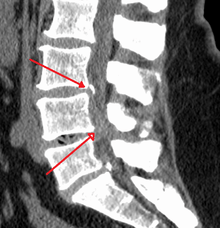

Spinal stenosis is an abnormal narrowing (stenosis) of the spinal canal that may occur in any of the regions of the spine. This narrowing causes a restriction to the spinal canal, resulting in a neurological deficit. Symptoms include pain, numbness, paraesthesia, and loss of motor control. The location of the stenosis determines which area of the body is affected.[1] With spinal stenosis, the spinal canal is narrowed at the vertebral canal, which is a foramen between the vertebrae where the spinal cord (in the cervical or thoracic spine) or nerve roots (in the lumbar spine) pass through.[2] There are several types of spinal stenosis, with lumbar stenosis and cervical stenosis being the most frequent. While lumbar spinal stenosis is more common, cervical spinal stenosis is more dangerous because it involves compression of the spinal cord whereas the lumbar spinal stenosis involves compression of the cauda equina.

The most common forms are cervical spinal stenosis, which are at the level of the neck, and lumbar spinal stenosis, at the level of the lower back. Thoracic spinal stenosis, at the level of the mid-back, is much less common.[1]

In lumbar stenosis, the spinal nerve roots in the lower back are compressed which can lead to symptoms of sciatica (tingling, weakness, or numbness that radiates from the low back and into the buttocks and legs).

Cervical spinal stenosis can be far more dangerous by compressing the spinal cord. Cervical canal stenosis may lead to myelopathy, a serious conditions causing symptoms including major body weakness and paralysis.[12] Such severe spinal stenosis symptoms are virtually absent in lumbar stenosis, however, as the spinal cord terminates at the top end of the adult lumbar spine, with only nerve roots (cauda equina) continuing further down.[13] Cervical spinal stenosis is a condition involving narrowing of the spinal canal at the level of the neck. It is frequently due to chronic degeneration,[14] but may also be congenital or traumatic. Treatment frequently is surgical.[14]